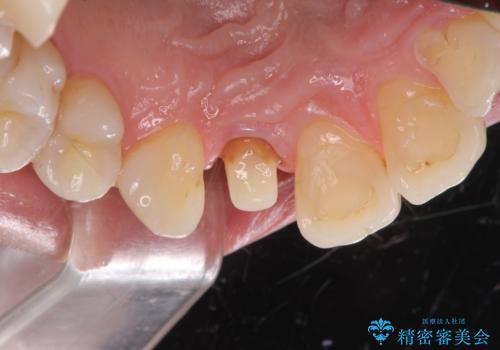

- 右上前歯の形と色が気になるとのことで来院された患者様です。

残っている歯に亀裂が多く走っていたため、クラウンでの修復処置を行います。

- 右上2 仮歯/11,000円 ファイバーコア/22,000円 ジルコニアクラウン(スタンダード)/121,000円 合計154,000円費用は治療当時の料金となります

歯ぐきの扱いに気を付けることで、術前よりも歯ぐきの位置が改善されました。